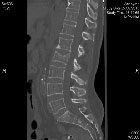

Cas Clinique

Source : Osteonews novembre 2015

Du ciment bien placé

Dr Jacques Fechtenbaum

Hôpital Cochin - Paris

Mme B, 53 ans, a fait une chute assez violente en sortant de sa douche, ayant entrainé une fracture de L2.

Cette fracture traumatique, non ostéoporotique, est importante, avec un enfoncement conséquent et asymétrique du plateau supérieur comme le montrent les images suivantes.